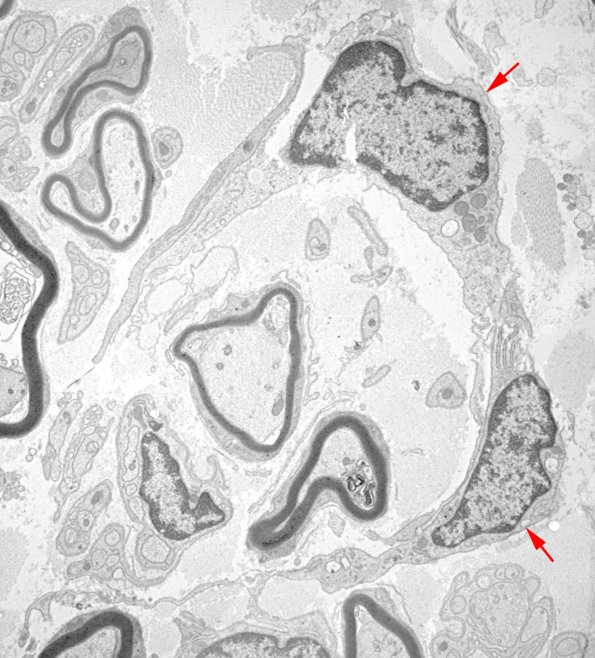

We settled on the cells representing fibroblasts, running out of other actors. (electron micrographs)